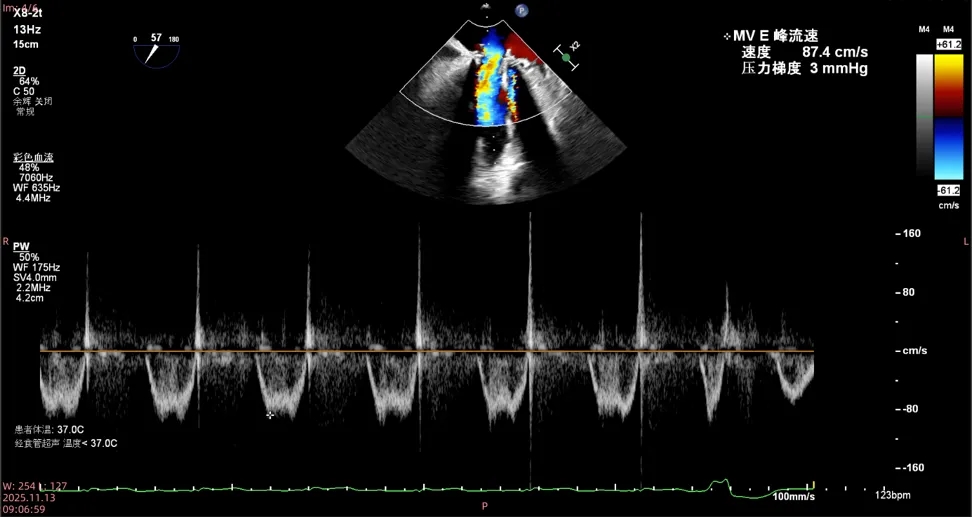

二尖瓣生物瓣退行性病变狭窄(重度)

二尖瓣

最大流速:87.4cm/s

平均压差:3mmHg